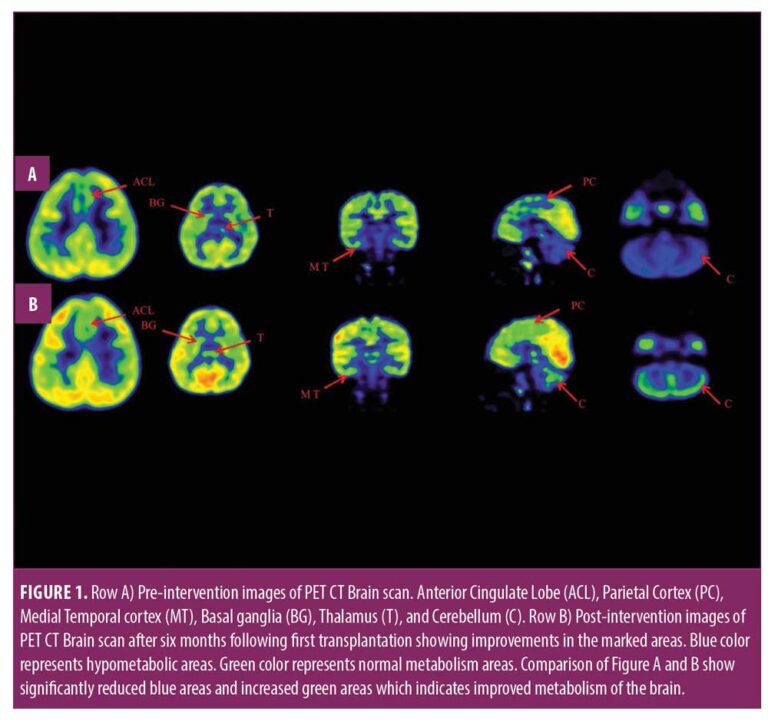

在認(rèn)知上,由于他定期上學(xué),他的注意力持續(xù)時(shí)間和坐姿耐受力也得到了改善。GMFM分?jǐn)?shù)從60.67提高到67。GMFCS等級(jí)由3級(jí)提升至2級(jí);FIM評(píng)分從97分提高到99分。比較第一次細(xì)胞治療之前和之后7個(gè)月期間進(jìn)行的腦部PET CT掃描結(jié)果,發(fā)現(xiàn)前扣帶回葉、頂葉皮層、內(nèi)側(cè)顳葉皮層、丘腦、基底神經(jīng)節(jié)和小腦(表1)。

這項(xiàng)研究表明,多種干細(xì)胞療法結(jié)合神經(jīng)康復(fù)可有效改善腦癱患者的粗大運(yùn)動(dòng)功能和功能獨(dú)立性。自體BMMNC多次移植后進(jìn)行強(qiáng)烈的神經(jīng)康復(fù)可加快神經(jīng)再生過(guò)程,這反過(guò)來(lái)又反映了患者殘疾程度和生活質(zhì)量的積極結(jié)果。PET CT掃描可以有效地用于監(jiān)測(cè)干預(yù)后細(xì)胞水平發(fā)生的變化。因此,多細(xì)胞療法是安全、可行的,并且可以有效地與腦癱的神經(jīng)康復(fù)相結(jié)合作為增強(qiáng)治療。